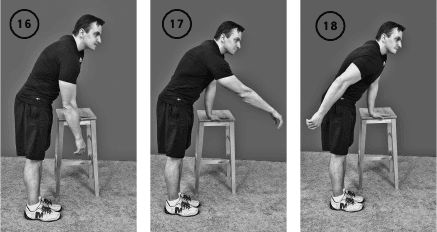

Упражнение «Маятник-плечо»

Исходное положение – стоя, одной рукой опираетесь о край стула, вторая свободно свисает.

Свободно качаете плечом вперед-назад, из стороны в сторону, движения подобны маятнику. Выполнять упражнение в течение 1 минуты.

Упражнение «Маятник-плечо» приводит к растяжению капсулы и связок плечевого сустава, расслаблению мышц плечевого сустава. Рекомендуем начинать и заканчивать гимнастику для плечевого сустава именно этим упражнением (ил. 16, 17, 18).